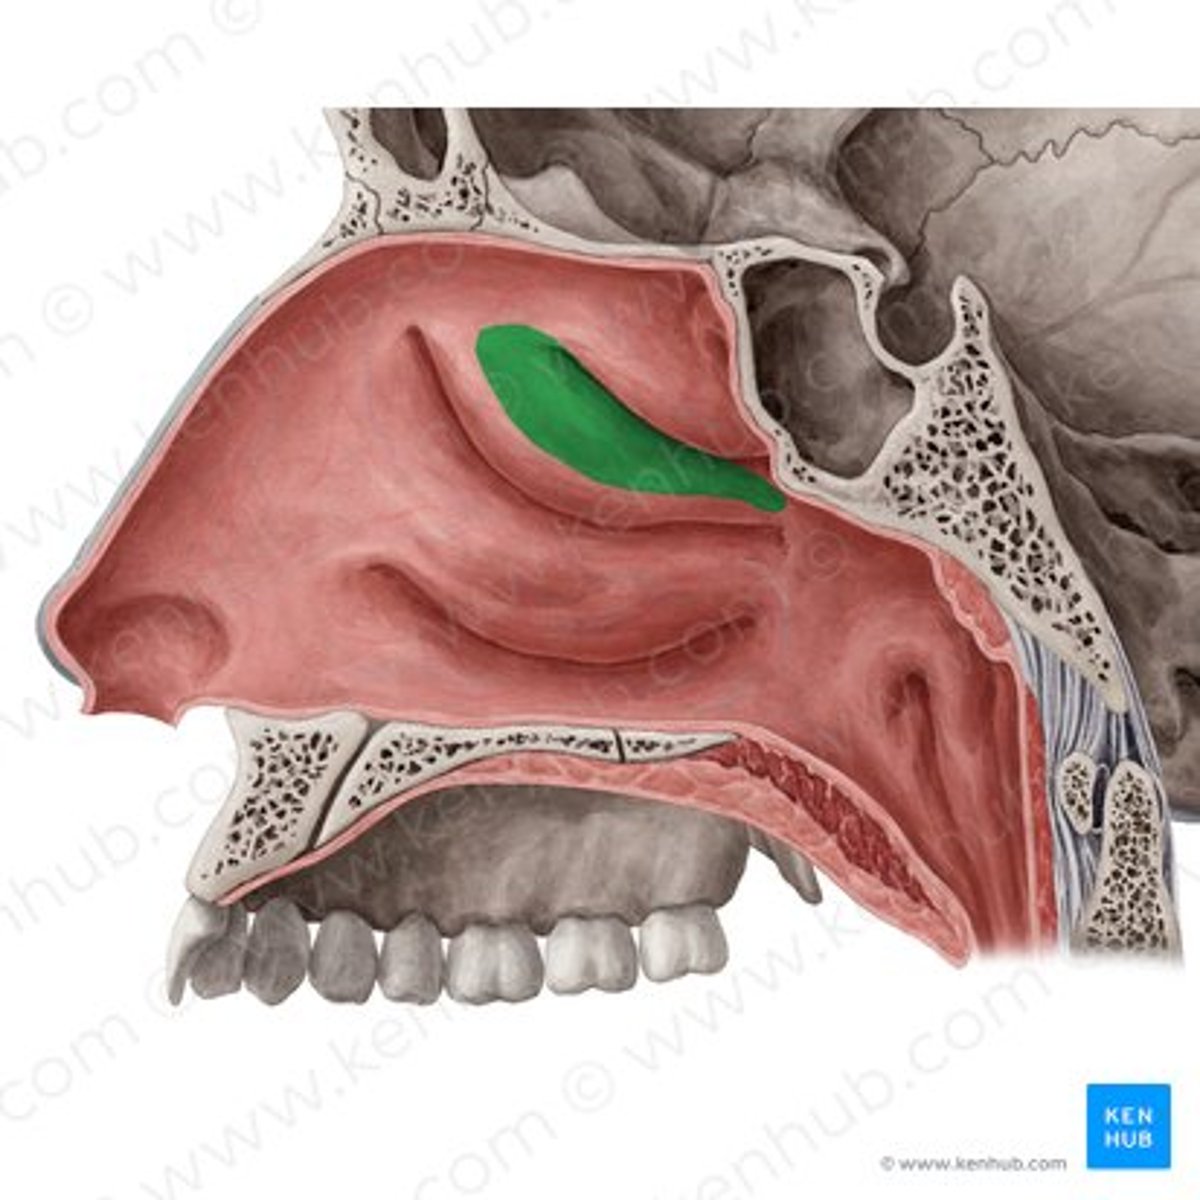

superior meatus

middle meatus

inferior meatus

inferior nasal concha

frontal sinus

nasal septum

hard palate

nasal bone

ethmoid bone (perpendicular plate)

palatine bone (horizontal plate)

maxilla (palatine process)

olfactory bulb (CN I)